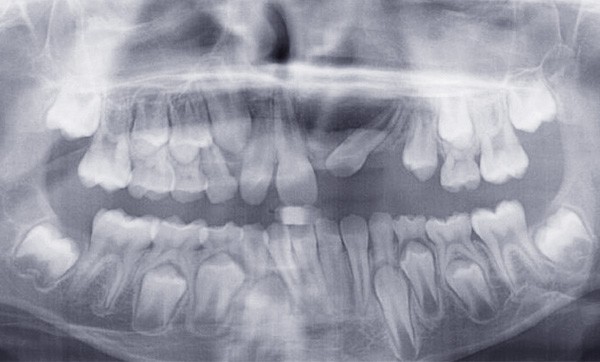

Le jeune Yoan 9 ans est adressé par son chirurgien maxillofacial, suite à l’exérèse d’un kyste bénin du maxillaire, et l’avulsion de 21 et 23 (fig. 1). L’apex de 22 a été soufflé par le kyste. La céphalométrie (fig. 2a et b) et l’examen clinique mettent en évidence une classe II squelettique par rétromandibulie, ainsi qu’une classe II dentaire. Le patient, est particulièrement perturbé par l’intervention qu’il vient de subir, et la coopération s’annonce difficile.

La gestion esthétique immédiate passe par un traitement orthodontique précoce, car la position de 22 (fig. 3) empêche toute restauration provisoire de l’édentement. Au vu du contexte, le choix thérapeutique se portera sur la simplicité, la rapidité, l’esthétique puis la réévaluation sur le long terme.

La 22 doit être remise sur l’arcade et le choix est fait de la mettre en lieu de 21 (fig. 4), puis de la maquiller pour temporiser en attendant l’évolution des autres dents définitives, et éviter le port d’une prothèse amovible transitoire (P.A.T.) tout en ramenant de l’os alvéolaire dans l’espace de 21.

L’interception dure 6 mois, et les attaches antérieures sont laissées en place et ligaturées (fig. 5) pour permettre une contention légère. On note la perte de la médiane.